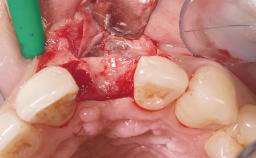

Immediate Flapless Placement of an Implant in a Maxillary Left Central Incisor Site

A 29-year-old female patient presented for treatment to replace the upper left central incisor tooth with an implant- supported restoration. The tooth had been intermittently symptomatic for the previous 12 months. The tooth had originally suffered trauma about 15 years previously. Several endodontic treatments had been performed, including an apicectomy procedure to retain the tooth. The patient was healthy and a non-smoker. She had reasonable expectations in regard to esthetic outcomes and the risk of marginal tissue recession following treatment. At medium smile, the gingival margins of the upper teeth were visible, with a display of 3 to 4 mm of the gingival margins. Gingival recession of tooth 21 and a discrepancy in the gingival levels between teeth 11 and 21 was observable during normal speech and smile.